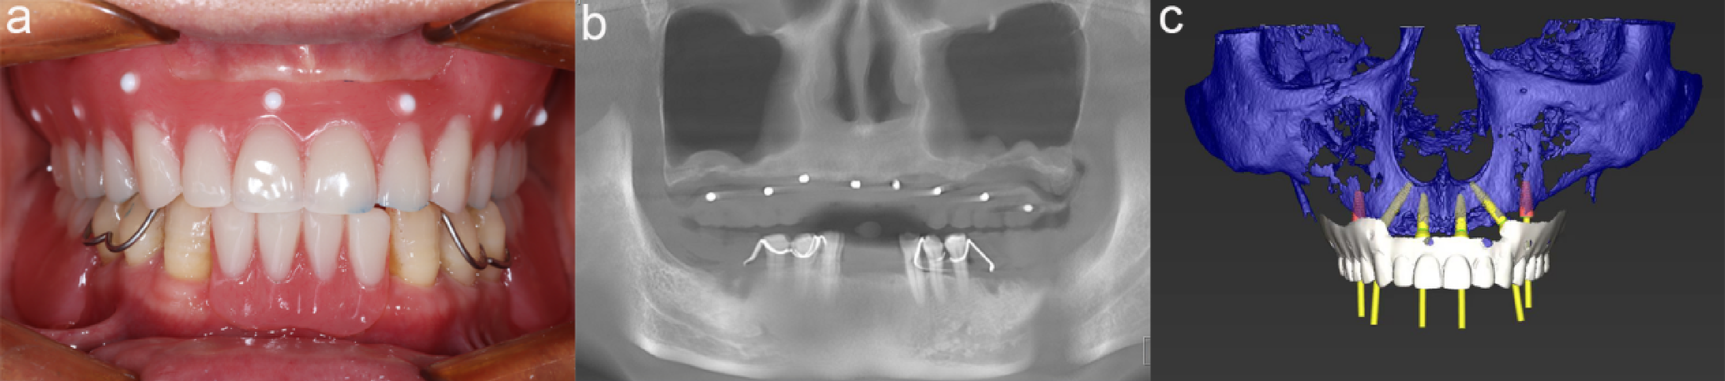

Preoperative design. (a) diagnostic denture (b) Preoperative cone beam computed tomography (CBCT) scan (c) Prosthetically guided implant design.